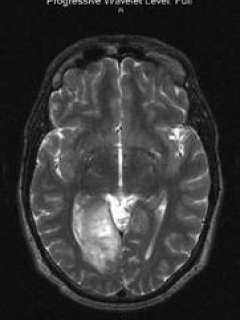

Robert is a 38 year-old right-handed man, born with congenital blindness of the left eye, who first presented with flashes of kaleidoscope-type color changes in his right eye around May 2004. His description of these symptoms were consistent with visual seizures, which are the abnormal, disorganized firing of neurons within the visual centers of the brain that may create the experience of flashes of light and/or color. Although he had had seizures in the past, these symptoms were new, so he underwent an MRI scan of his brain. MRI at the time revealed a mass in the occipital lobe, the main vision center of the brain, on the right side. After a trial of medical management with anti-seizure medications and serial MRI scans to see if the mass was actively growing, radiologic evidence of disease progression in September 2005 brought him to Ronald Reagan UCLA Medical Center in search of surgical treatment.

Dr. Linda Liau met Robert and decided that surgical resection of the mass would be the most appropriate treatment choice given his symptoms and increasing size of the lesion. As the mass was located in an area that would result in obvious neurologic deficits if disrupted (visual cortex), preoperative functional MRI (fMRI) and diffusion tensor imaging (DTI) data was obtained in order to help map out the relation of the mass to critical visual fibers for navigation in the OR. This helps the surgeon intraoperatively by guiding resection and avoiding areas critical for neurologic function. [Purple = visual fibers; yellow = tumor].

Preoperative functional MRI T2 axial view:

Preoperative functional MRI T2 axial view of Robert's brain